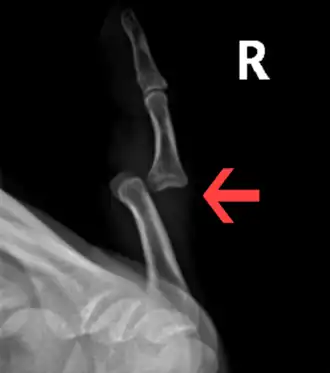

Dislocation of the left index finger -

Radiograph of right fifth phalanx bone dislocation -